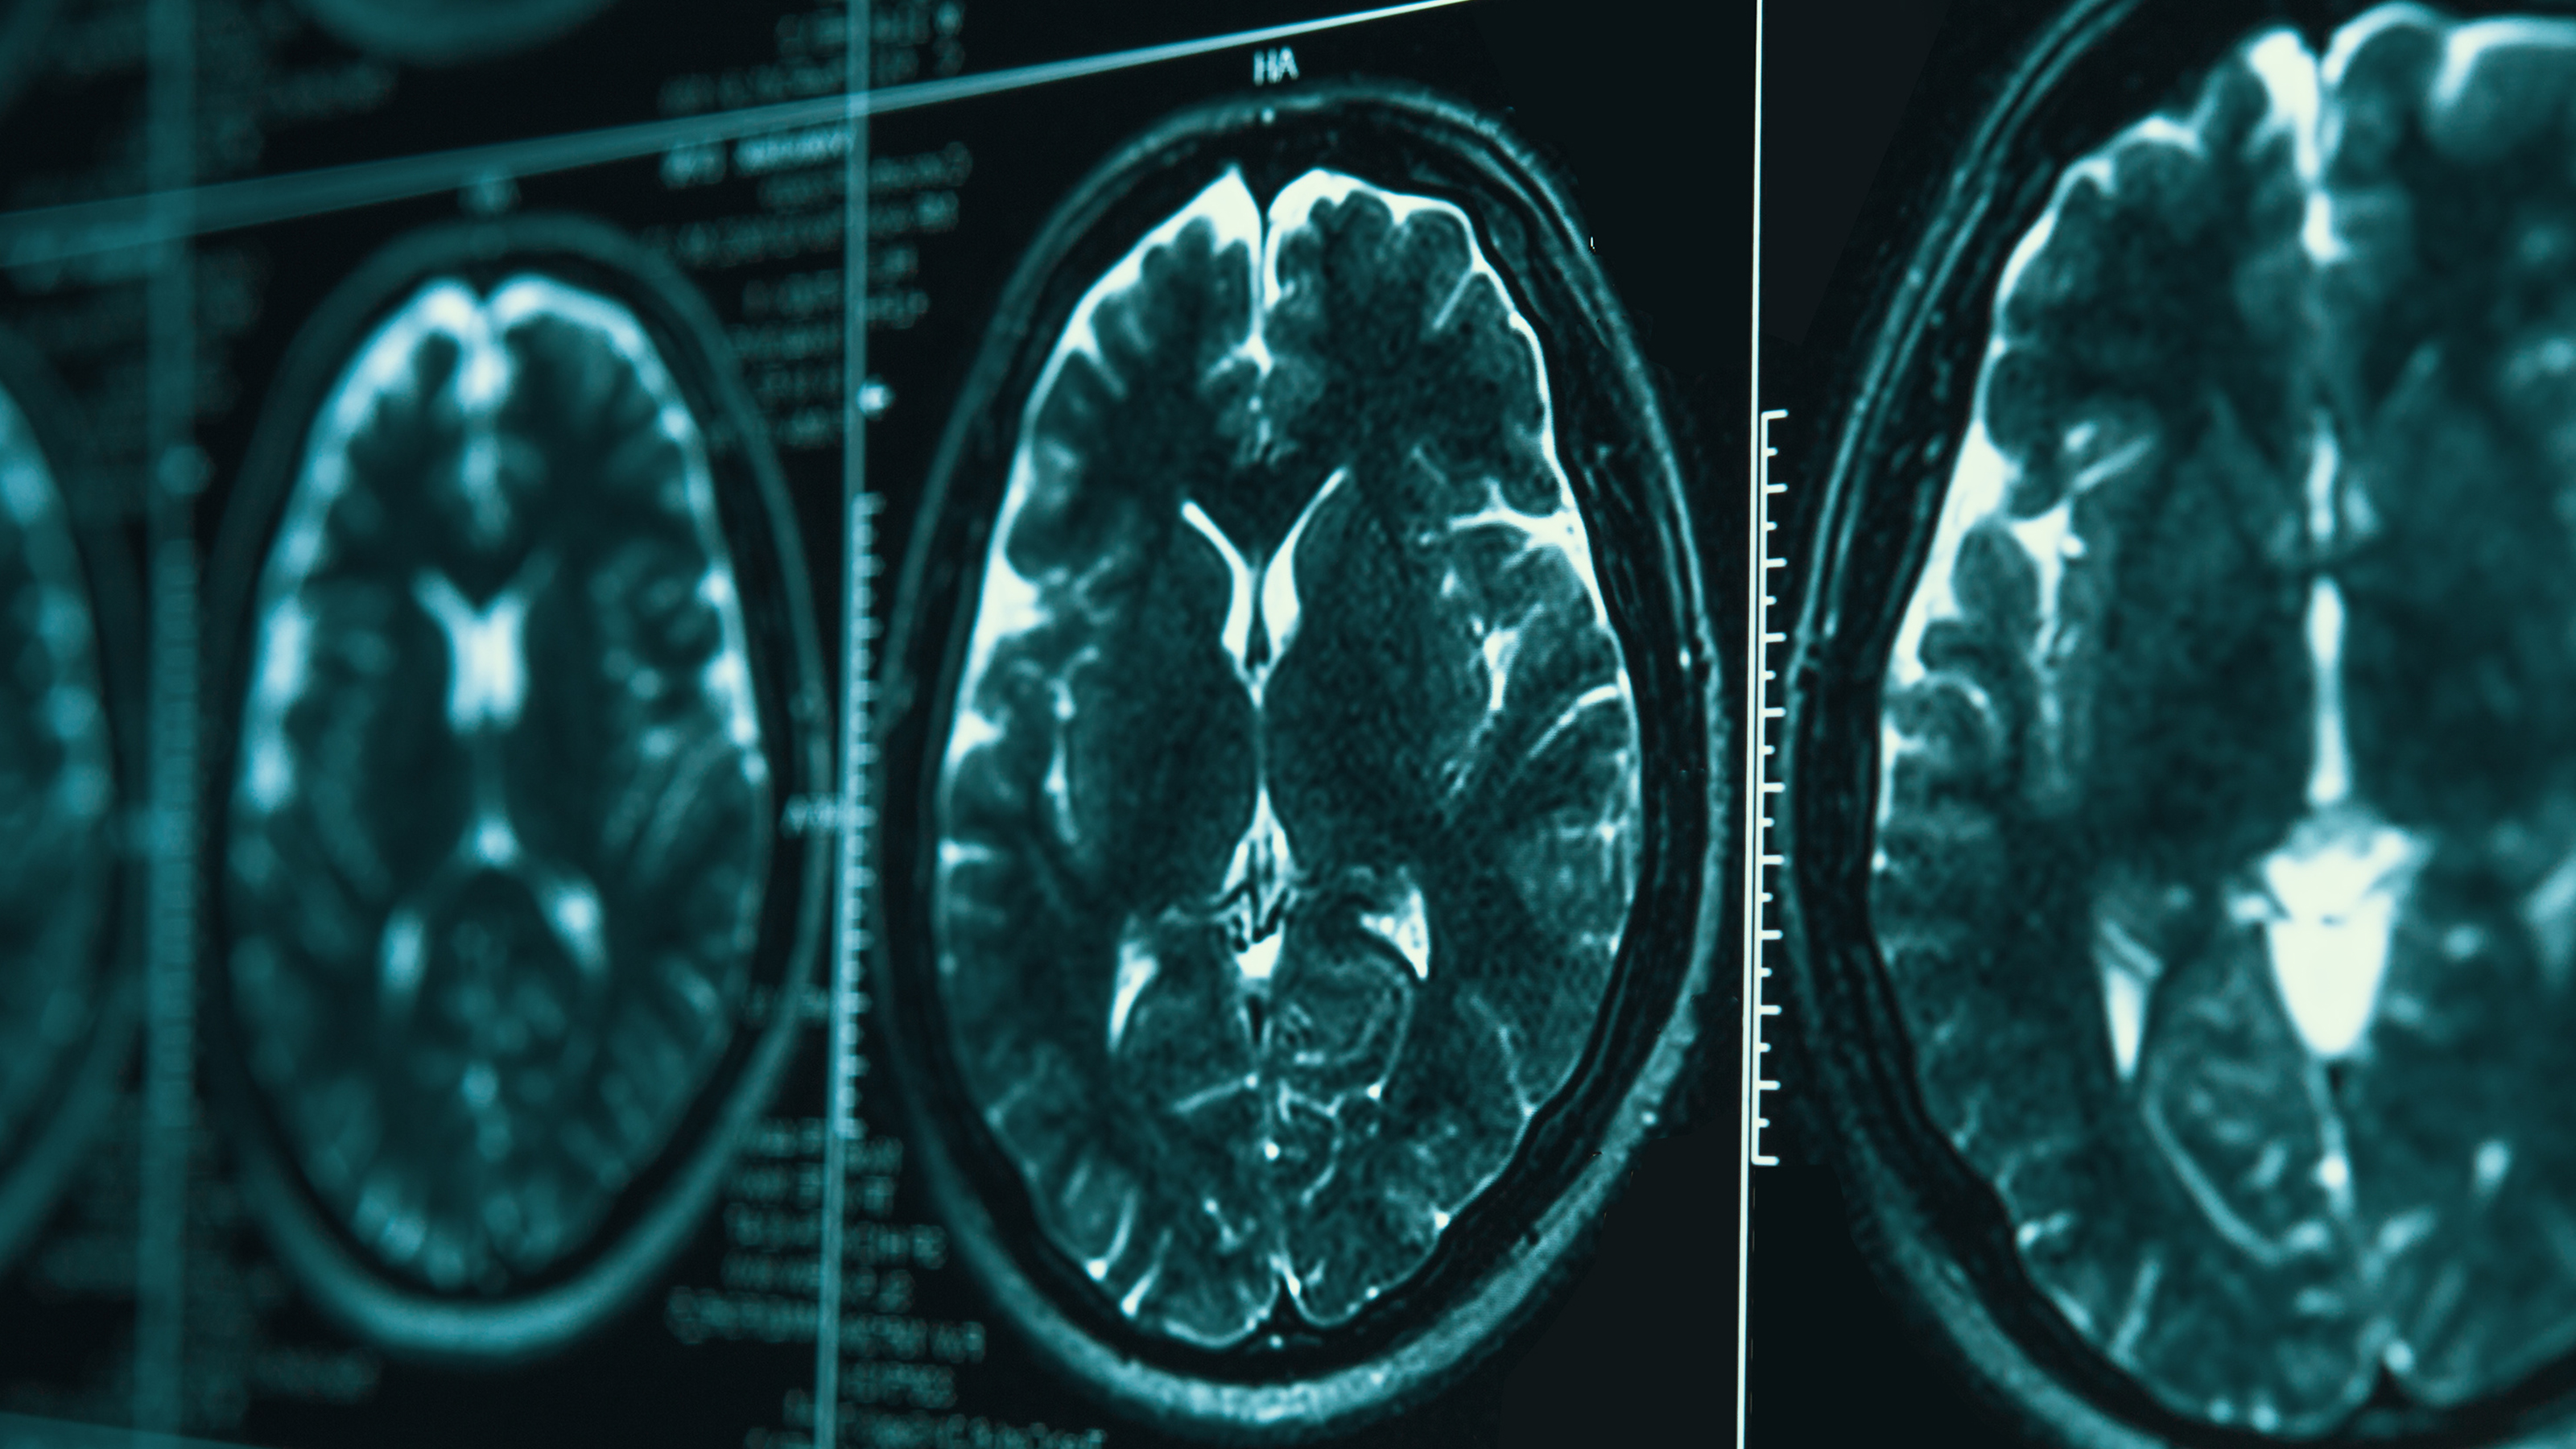

Can AI predict which depression treatment is most effective?

Artificial intelligence-powered algorithms that analyze brain scans are showing promise in helping doctors find an effective depression treatment on the first try.